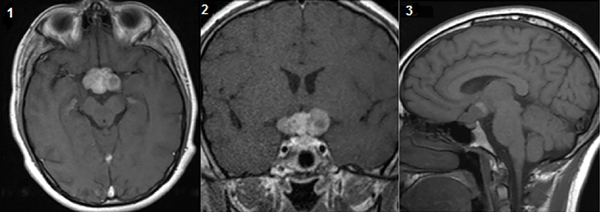

Se realiza RM de encéfalo en la cual se evidencia lesión supraselar de aproximadamente 2,5 cm de diámetro superior y 3,5 cm de diámetro anteroposterior con realce heterogéneo tras la administración de contraste endovenoso. A su vez, se evidencia compromiso del quiasma y nervios ópticos (Figura 1 – 3). Se presentan detalles del campo visual (Figura 4).

Figura 1, 2, 3. Resonancia Prequirúrgica.